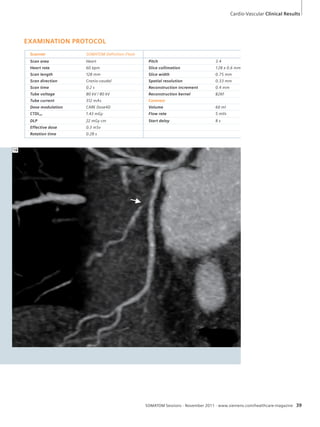

breath

hold: Note

comparable

image quality.

5 Coronal

reformation of

CTPA in lung

window: note